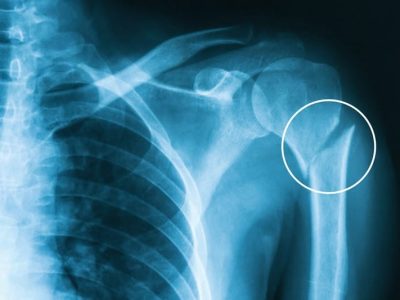

What is a Simple Elbow Dislocation? Simple Elbow Dislocation: This happens when the elbow joint (where the upper arm bone meets the forearm bones) gets dislocated without any broken bones. Complex Instability: This occurs when there are broken bones along…